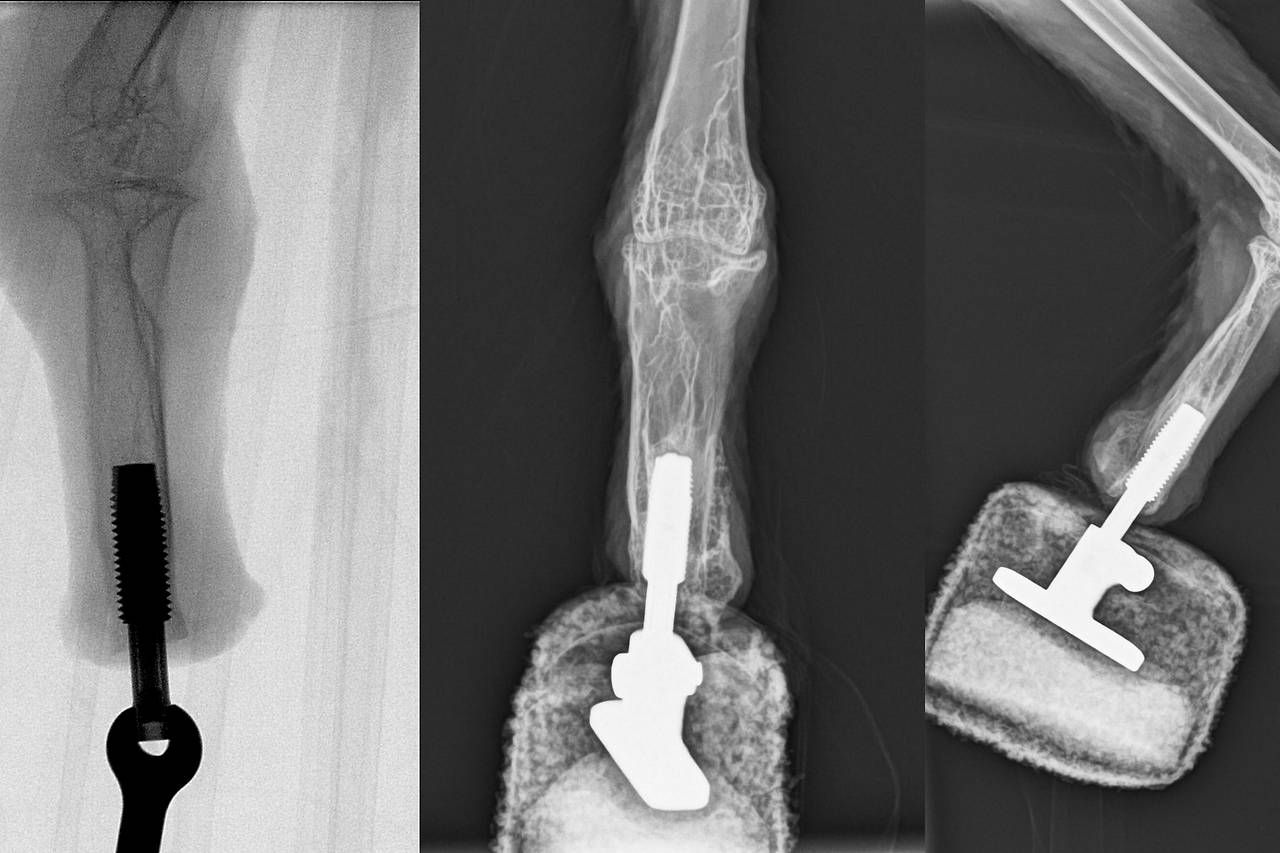

Der neue Fuß des Bartgeiers.

MEDUNI WIEN/ARBEITSGRUPPE OSKAR ASZMANN

Vogel wäre sonst gestorben

„Nach einer klinischen Visite in Haringsee war klar, dass der seltene Vogel nicht lange in der aktuellen Situation überleben würde. Wir konzipierten und fertigten ein eigenes Knochenimplantat an, welches bei der OP am Stumpf eingesetzt wird", erklärt Oskar Aszmann. Die Operation bei dem Bartgeier wurde gemeinsam mit Rickard Branemark vom Center for Osseointegration Research (San Francisco) am Zentrum für Biomedizinische Forschung an der MedUni Wien (Leiter: Bruno Podesser) erfolgreich durchgeführt.

Erster bionischer Vogel

Die Rehabilitation und prothetische Versorgung erfolgte wieder in Haringsee. „Schon nach drei Wochen erfolgten die ersten Gehversuche und nach sechs Wochen die vollständige Belastung. Heute kann der Bartgeier wieder mit zwei Füßen und als erster ‚bionischer Vogel‘ landen und gehen“, sagt Aszmann, der vor allem durch seine bahnbrechenden Arbeiten zu bionischen Händen weltweite Bekanntheit erlangte.